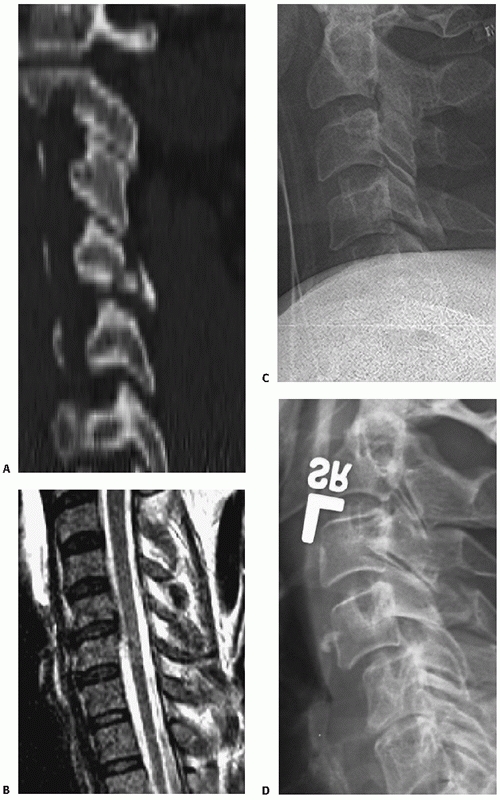

![]() |

|

FIGURE 42-1

The Power ratio is calculated by dividing the distance between the basion and the posterior C1 arch by the distance between the opisthion and the anterior C1 arch. A ratio greater than 1 is suggestive of an atlanto-occipital dislocation. |

FIGURE 42-5 (continued) B. Recommended measurement technique of odontoid angulation.

FIGURE 42-6 Endplate method of measuring C2-C3 angulation.

FIGURE 42-7 Posterior vertebral body tangent line method for C2-C3 angulation measurement.

FIGURE 42-8

The Cobb method of measuring cervical kyphosis. A line is drawn along the superior endplate of the superior adjacent uninjured vertebrae; a second line is drawn along the inferior endplate of the inferior adjacent uninjured vertebrae. The angle subtended between the two is then measured. |

FIGURE 42-9

The posterior vertebral body tangent method of measuring cervical kyphosis. A line is drawn along the posterior aspect of the adjacent vertebral vertebral bodies. The angle subtended between the two is then measured. |